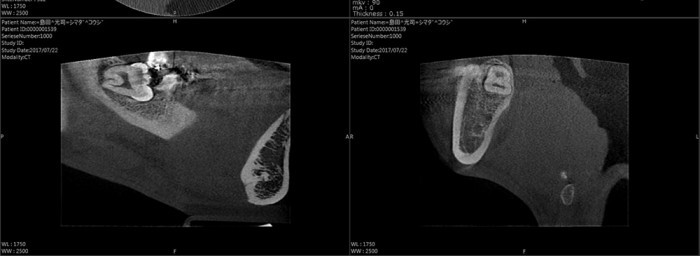

歯科用CTで正確・安全な歯科医療を提供します。

当院では一人ひとりの患者様のお口の状態を正確に把握し、より精度の高い安全な治療を提供するために歯科用CTを導入しています。従来のレントゲン撮影の1/10の被曝量を実現し、お子様にも安心してお使いいただける身体に優しいCTを使用しています。また、こちらのCTで撮影されたデータは迅速にデジタル処理されるため、撮影した写真を患者様と共有しながらお話しするまで患者様をお待たせすることがありません。当院では患者様が本当に安心して診療を受けていただける環境作りに努力を惜しみません。